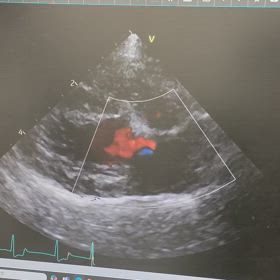

心臓手術して一年経ちました。

術後6カ月検診